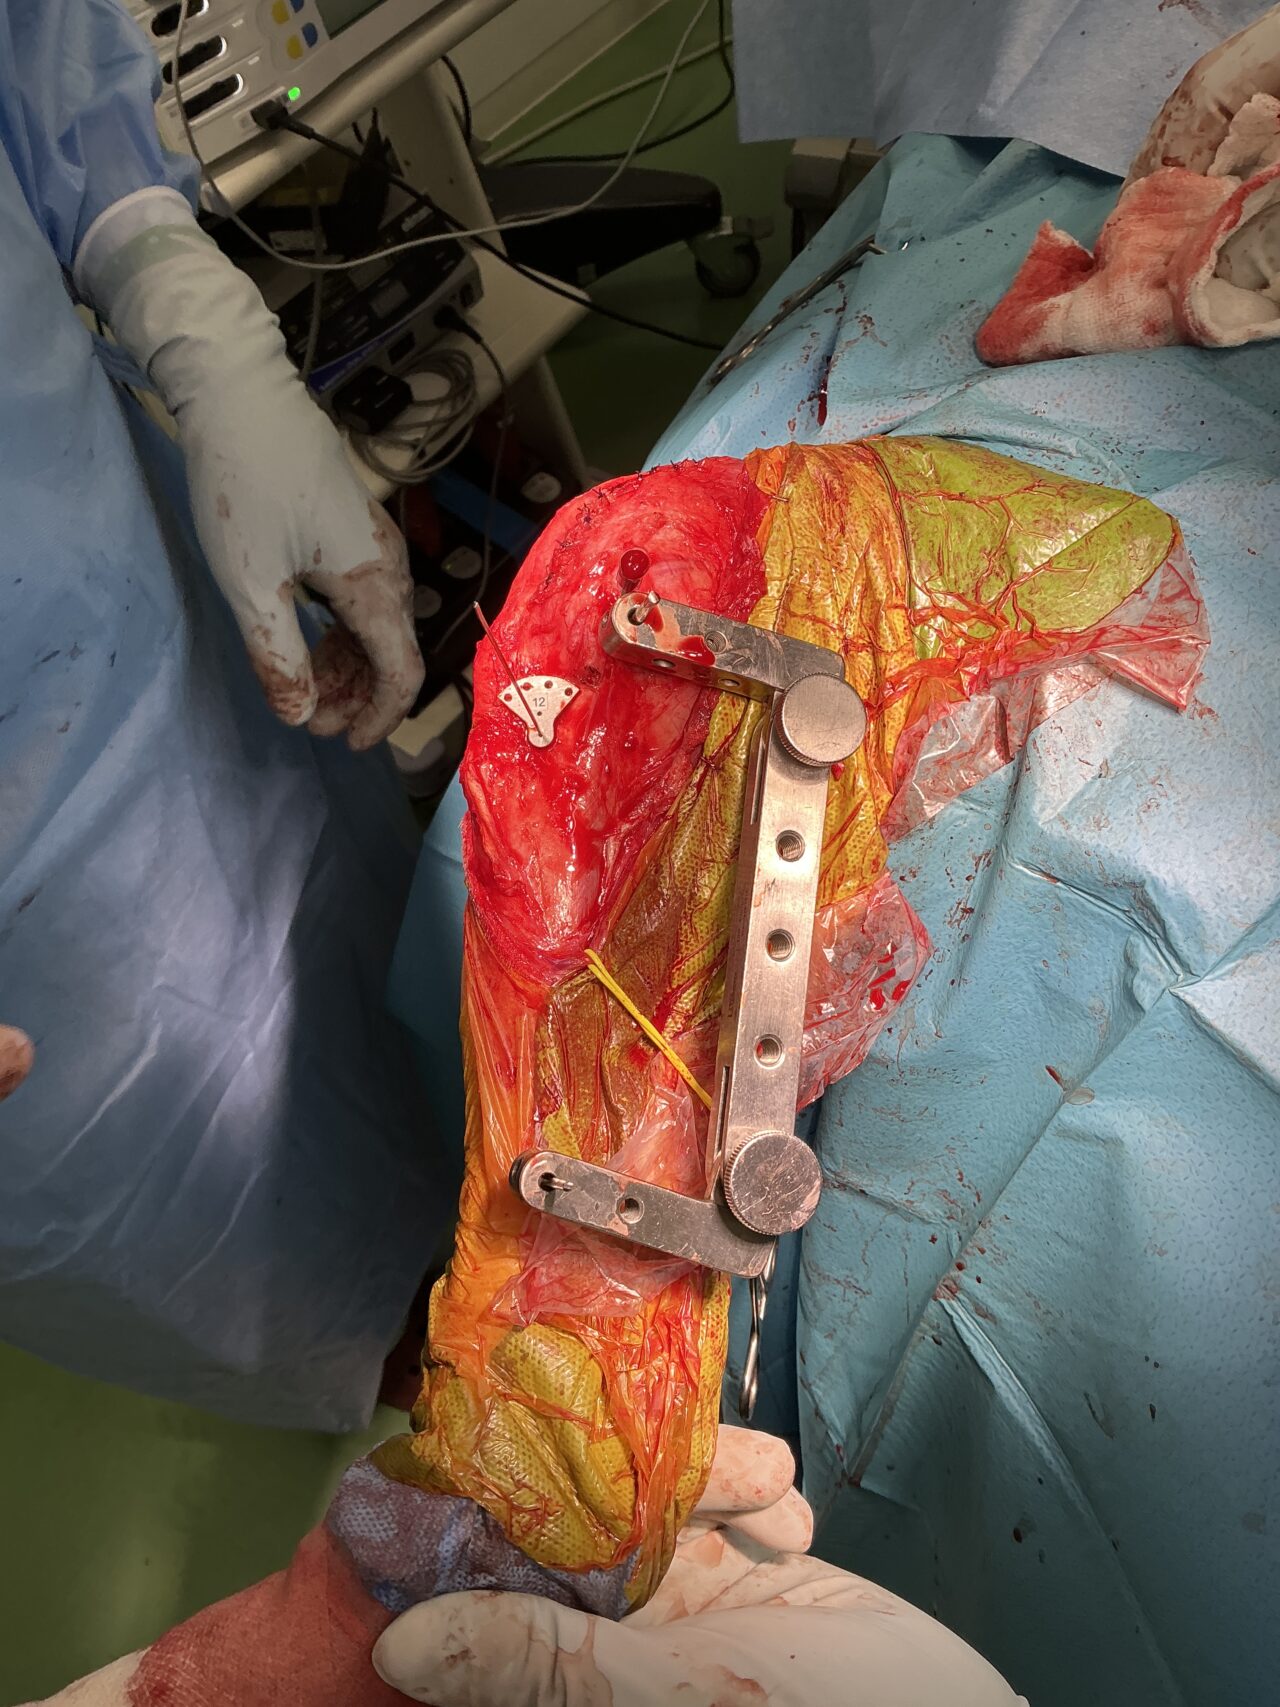

大型犬の前十字靭帯疾患(慢性経過)に対するCBLO #254 大型犬のCrCLDの患者さんに3.5 Rita Locking CBLOで対応しました。今後はリハビリテーションが非常に重要になります。生涯にわたって膝関節のケアを行なっていく必要があります。 症例カテゴリー 放射線治療整形外科軟部組織外科脳神経外科内科腫瘍外科救急・集中治療リハビリテーション科腫瘍内科内視鏡科脳神経科呼吸器外科中医・漢方猫の腎移植循環器科